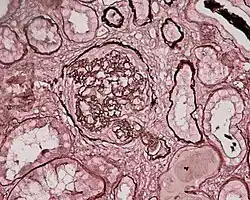

Membranoproliferative

Membranoproliferative GN (MPGN), also known as mesangiocapillary glomerulonephritis,[2]: 502 is characterised by an increase in the number of cells in the glomerulus, and alterations in the glomerular basement membrane. These forms present with the nephritic syndrome, hypocomplementemia, and have a poor prognosis. Three subtypes have been proposed:[4]: 552–553

- Type 1 MPGN is caused by immune complex deposition in the mesangium and subendothelial space, typically secondary to systemic lupus erythematosus, hepatitis B and C, or other chronic or recurring infections. Circulating immune complexes may activate the complement system, leading to inflammation and an influx of inflammatory cells.[4]: 552–553

- Type 2 MPGN, also known as Dense Deposit Disease, is characterised by an excessive activation of the complement system. The C3 Nephritic Factor autoantibody stabilizes C3-convertase, which may lead to an excessive activation of complement.[4]: 553 Type 2 MPGN is a subgroup of C3 glomerulopathy, a newly proposed diagnosis which also encompasses C3 Glomerulonephritis (C3GN).[7][8]

- Type 3 MPGN, which is caused by immune complex deposition in the subepithelial space.